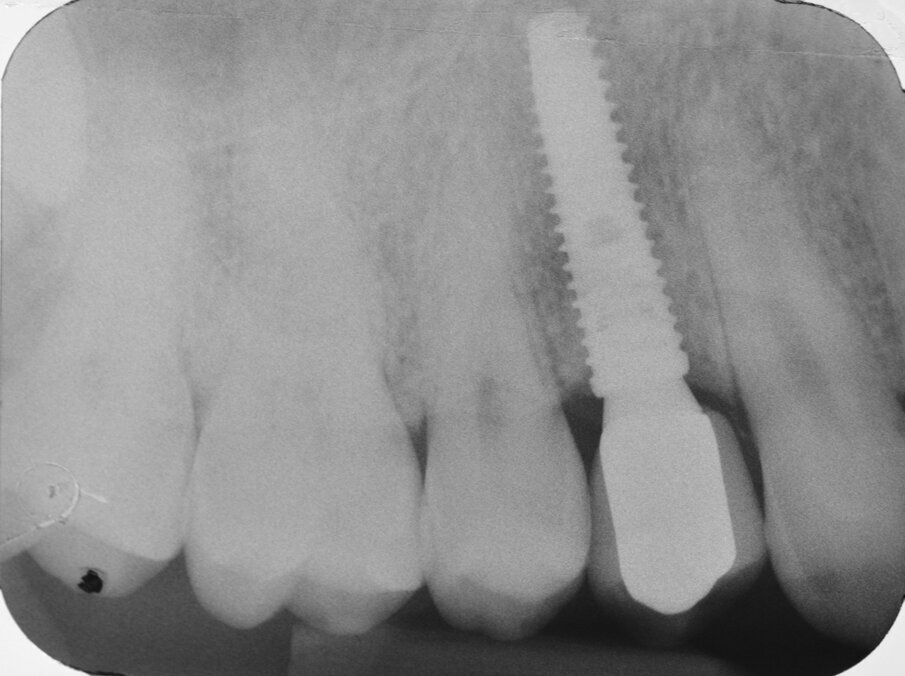

All’esame obiettivo viene si evidenzia una frattura verticale a carico dell’elemento in questione (Figg. 1, 2) che pone indicazione assoluta all’estrazione dentaria; per evitare di aggravare l’inevitabile contrazione della cresta ossea alveolare, si decide di eseguire l’estrazione dell’elemento fratturato senza sollevare alcun lembo. Viene effettuato un esame radiografico endorale allo scopo di visualizzare la morfologia della radice dentaria e i suoi rapporti con le strutture viciniori. (Fig. 3)

Fig. 3 - Esame radiografico endorale preoperatorio.